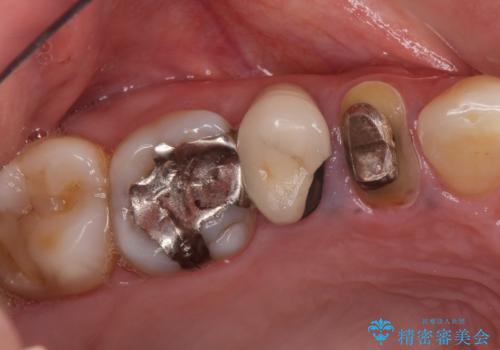

オールセラミッククラウン 咬むと痛む奥歯の治療